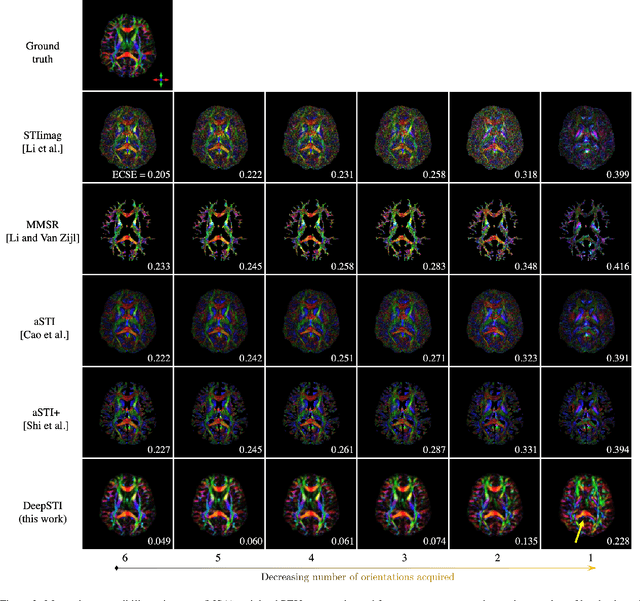

Abstract:Susceptibility tensor imaging (STI) is an emerging magnetic resonance imaging technique that characterizes the anisotropic tissue magnetic susceptibility with a second-order tensor model. STI has the potential to provide information for both the reconstruction of white matter fiber pathways and detection of myelin changes in the brain at mm resolution or less, which would be of great value for understanding brain structure and function in healthy and diseased brain. However, the application of STI in vivo has been hindered by its cumbersome and time-consuming acquisition requirement of measuring susceptibility induced MR phase changes at multiple (usually more than six) head orientations. This complexity is enhanced by the limitation in head rotation angles due to physical constraints of the head coil. As a result, STI has not yet been widely applied in human studies in vivo. In this work, we tackle these issues by proposing an image reconstruction algorithm for STI that leverages data-driven priors. Our method, called DeepSTI, learns the data prior implicitly via a deep neural network that approximates the proximal operator of a regularizer function for STI. The dipole inversion problem is then solved iteratively using the learned proximal network. Experimental results using both simulation and in vivo human data demonstrate great improvement over state-of-the-art algorithms in terms of the reconstructed tensor image, principal eigenvector maps and tractography results, while allowing for tensor reconstruction with MR phase measured at much less than six different orientations. Notably, promising reconstruction results are achieved by our method from only one orientation in human in vivo, and we demonstrate a potential application of this technique for estimating lesion susceptibility anisotropy in patients with multiple sclerosis.